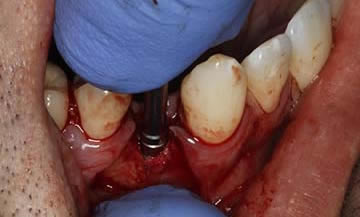

This gentleman had lost his heavily restored UL4 and decided to close the space with an implant retained crown. The thin buck-palatal width required careful placement to avoid fenestration bucally. A tooth bourn position guide was used to place the implant predictably and within the aesthetic envelope. The implant was restored after three months of osseointegration with a bonded crown.